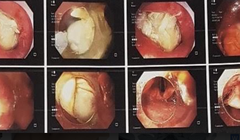

Hình ảnh xương gà mắc trong cổ họng bệnh nhân (Ảnh - BVCC)

Hóc xương cánh gà, người đàn ông phải nhập viện cấp cứu

VietTimes – Các bác sĩ ở Bệnh viện (BV) Hữu nghị Việt Đức vừa cấp cứu kịp thời cho 1 bệnh nhân bị hóc xương cánh gà.